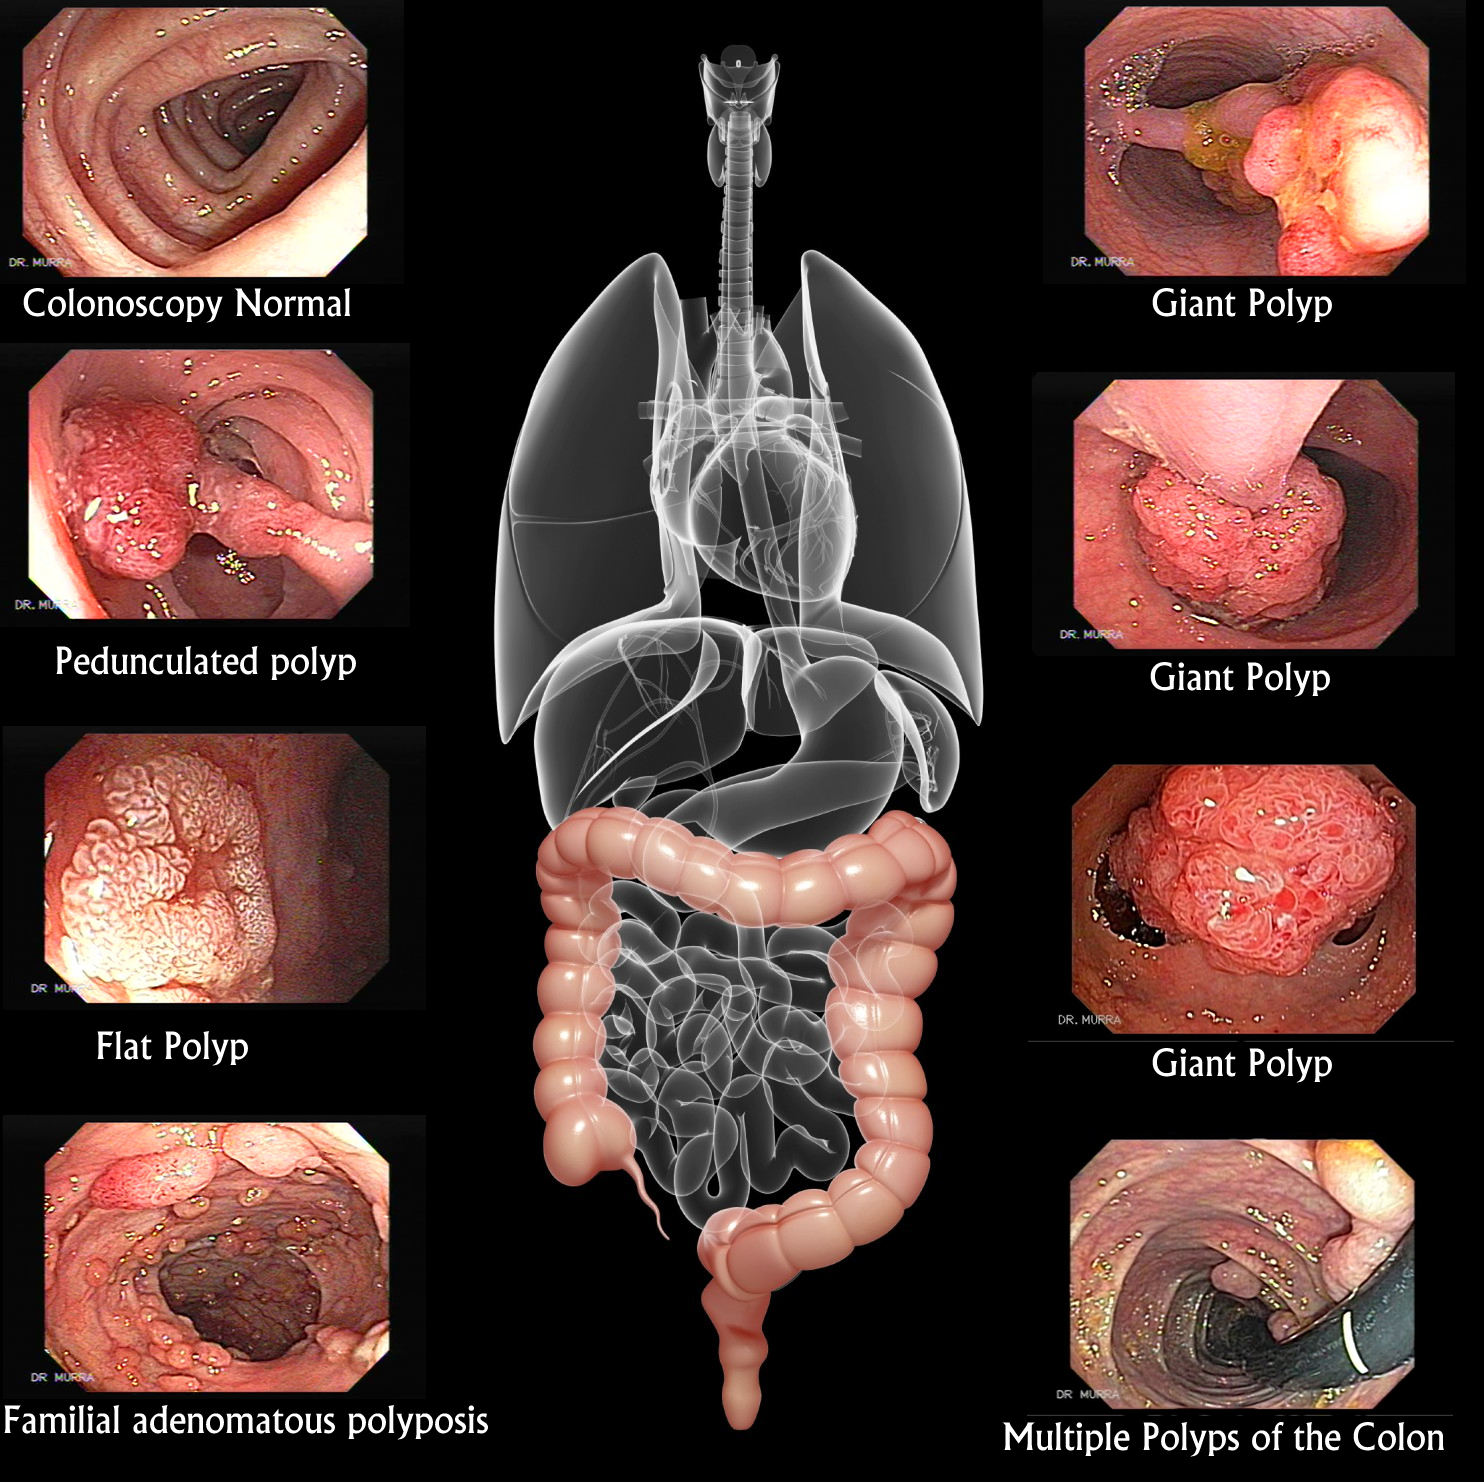

Colonic Polyps

Polypectomy 1

Polypectomy 2

Polypectomy 3

Familial Polyposis

Familial Polyposis II

Normal Colon